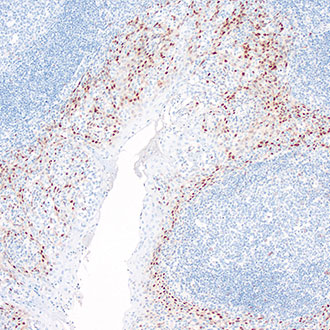

IHC

免疫组织化学(IHC)